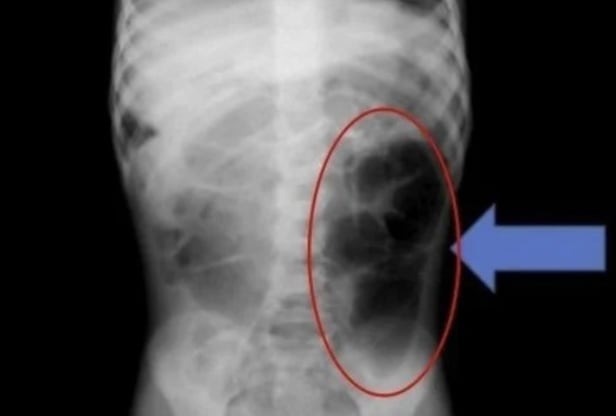

Búi tóc được phát hiện trong bụng bé gái.

Nhóm y tế phát hiện ra rằng sợi tóc không chỉ nằm trong dạ dày mà còn lan đến ruột non. Họ cho biết: "Nếu bệnh nhi có các triệu chứng dai dẳng như đau bụng tái phát, nôn mửa hoặc chán ăn kéo dài, cần phải xem xét khả năng có dị vật trong đường tiêu hóa".